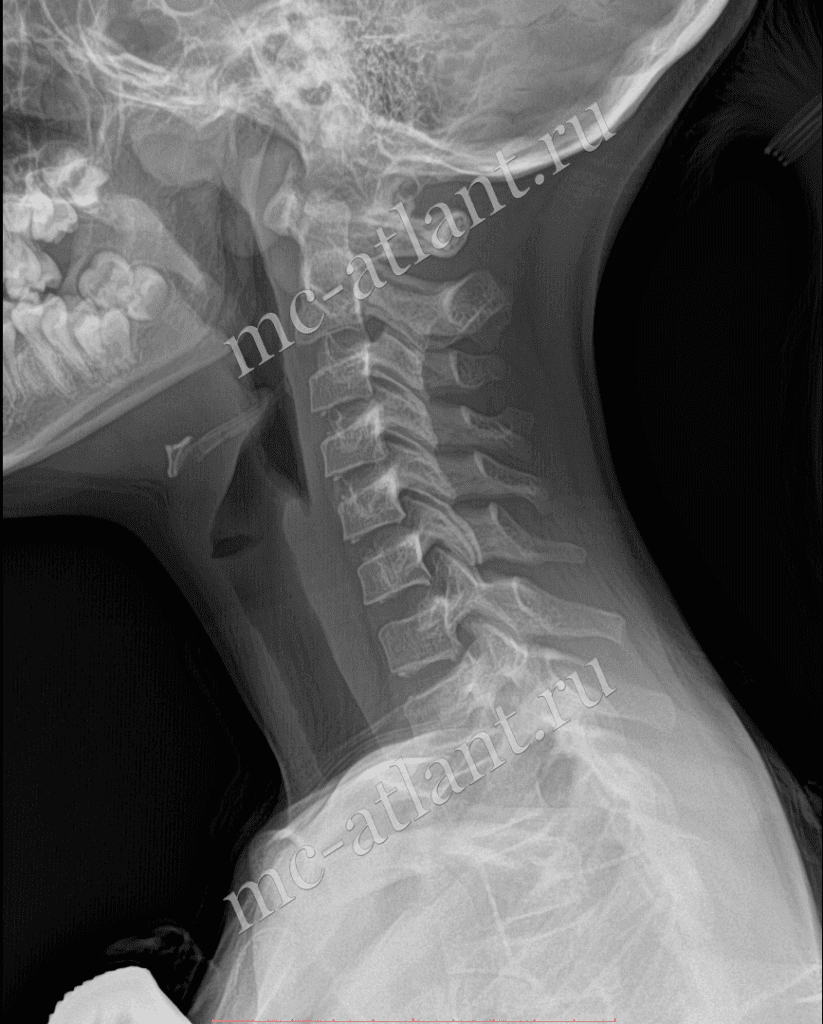

Рентген шейных позвонков при спина бифида

Раздел: Фотозарисовки